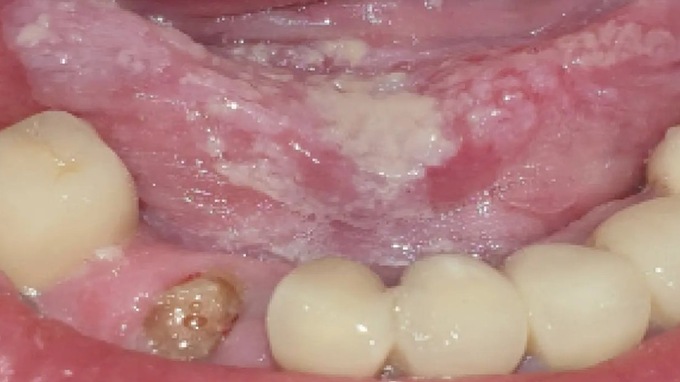

● Savoir les effets de ces traitements sur la sphère buccale et identifier les risques pour sa pratique.

● Prise en charge des complications.